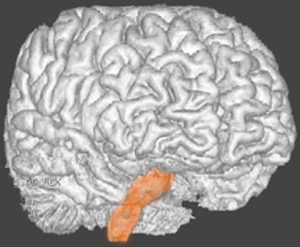

脳幹部の解剖図

- 脳の底面からしか見えないのでいろいろな角度から見ています